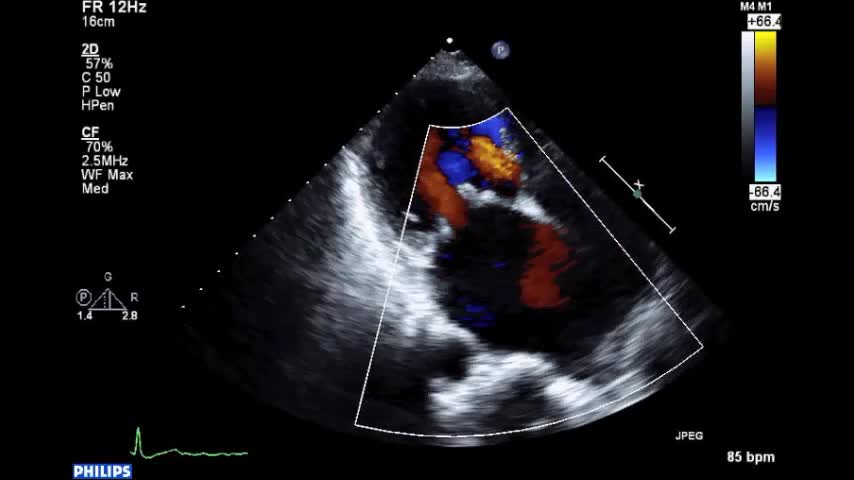

• 症例2 60代男性.僧帽弁逆流症

• 図5 僧帽弁後尖P2 逸脱によるMR a 胸骨右縁第2...

• 図5 僧帽弁後尖P2 逸脱によるMR a 心尖